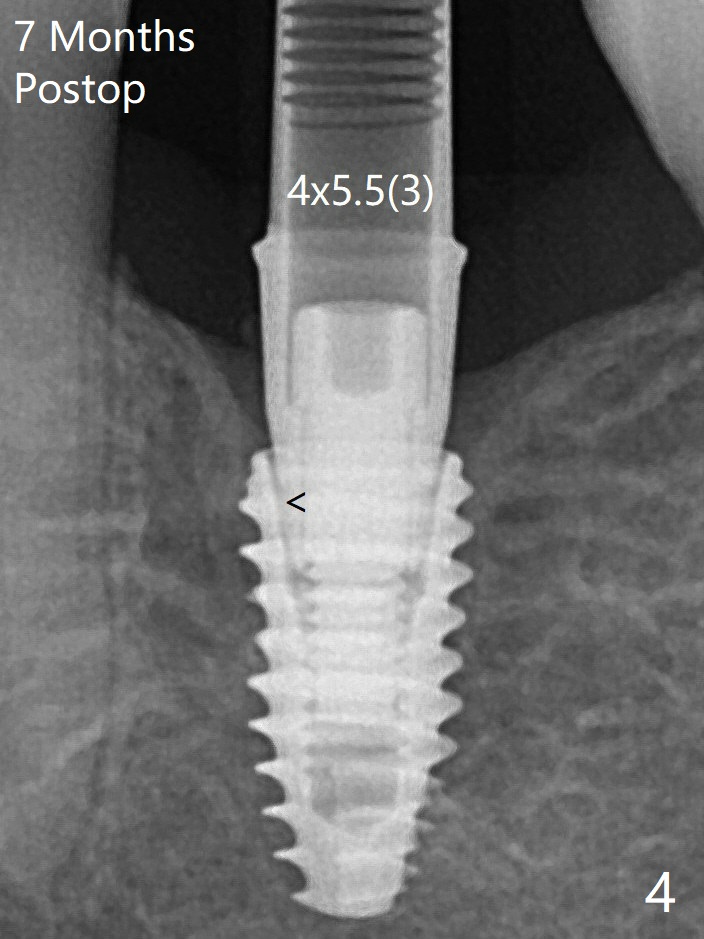

局麻下使用4.6毫米Profile钻头后(去除软硬组织阻挡),4.5毫米修复基台顺利就位(图五)。手拧紧螺丝顺手,不发出响声。因此第一次手术应该使用Profile钻头。